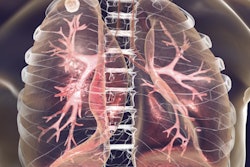

Where bacteriological trial may be inconclusive, artificial intelligence (AI) can assist in diagnosing tuberculosis (TB). New research shows that TB can be consistently detected on lateral chest x-rays by an ensemble of two different types of deep-learning networks. The findings were published online recently in Frontiers in Genetics.

As part of the End TB strategy, the World Health Organization (WHO) has recommended the use of chest x-ray as a screening and triage tool where bacteriological diagnostic tests are unclear. Inconclusive TB tests are common in children due to their lower bacteria counts, according to the WHO. The strategy also states that lateral chest x-ray views may be needed in cases of a challenging bacteriological confirmation in younger children.

Lateral chest radiographs help to detect clinically suspected pulmonary TB, particularly in children. A number of studies have shown the benefit of lateral chest x-rays in, for example, identifying mediastinal or hilar lymphadenopathy. They also help to provide information on the thoracic cage, pleura, lungs, pericardium, heart, mediastinum, and upper abdomen, according to the researchers.

“These studies underscore the importance of using lateral [chest x-ray] projections as they carry useful information on disease manifestation and progression; hence, this study aims to explore these least studied types of [chest x-ray] projection (the lateral) and propose a novel approach for detecting TB-consistent findings,” the authors wrote.